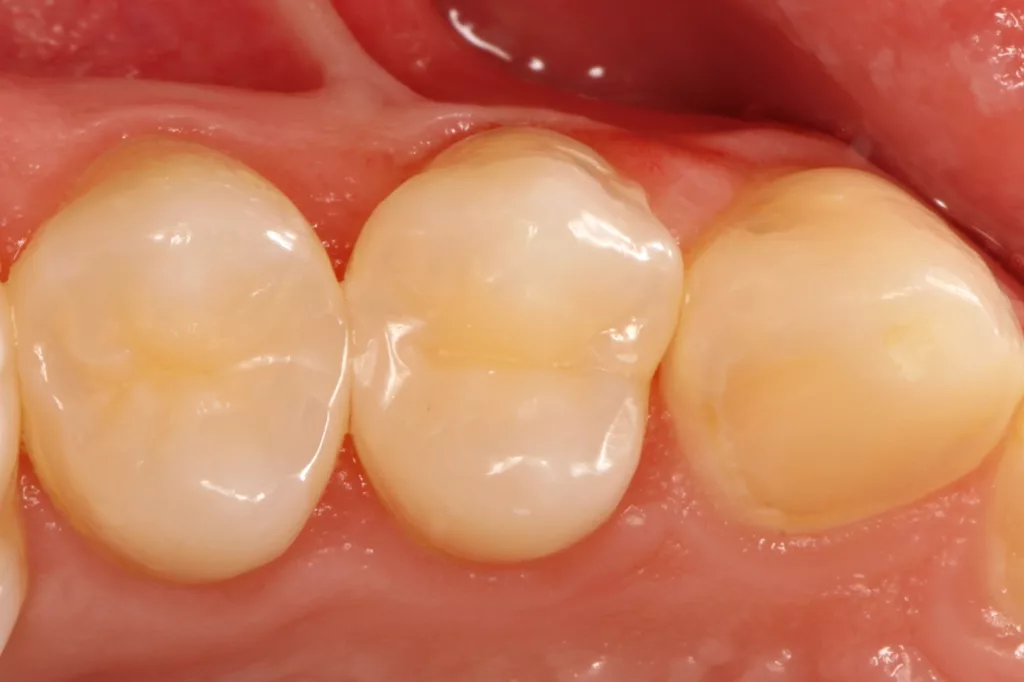

Dass mit sehr dünnen Matrizenfolien auch zwei benachbarte Kavitäten gleichzeitig versorgt werden können, zeigt der Fall des 19-jährigen Patienten an den Zähnen 24 und 25. Die zeitgleiche Versorgung zweier benachbarter Kavitäten hat den Vorteil des ökonomischeren Arbeitens und der Reduktion einer Kontamination der zweiten Kavität mit dem Adhäsiv, bei dessen Verblasen in der als erste versorgten Kavität: Da es beim Matrizenwechsel nahezu immer zu einer Blutung oder sonstigen Kontamination kommt, muss eine erneute Reinigung bzw. Nachpräparation der zweiten Kavität vorgenommen werden. Ein ledigliches Ausspülen vor einer adhäsiven Versiegelung der Kavität dürfte ineffizient sein, da sich die Phosphorsäurekonditionierung der Schmelzränder durch die Verklebung der Oberfläche mit dem verblasenen Adhäsiv aus der erstversorgten Kavität kaum suffizient gestalten lassen dürfte.

Es müssten die Klebeflächen somit sekundär noch einmal angefrischt werden, was wiederum aufgrund der Enge in dem minimalinvasiven Kavitätenbereich einen erneuten und nicht ganz so einfachen Arbeitsschritt darstellt. Aus diesem Grunde ist die zeitgleiche Versorgung derartiger Approximalläsionen kontaminationstechnisch einfacher zu bewerkstelligen und somit vorzuziehen – vorausgesetzt der Approximalkontakt ist ausreichend stark. Dies wurde in dem vorliegenden Fall durch die Verwendung zweier sehr dünner (0,03 mm) Teilmatrizenfolien (QuickmatFLEX Titan, Polydentia, Schweiz, Abb. 20 und 21) sichergestellt. Die hervorragende Separationskraft des verwendeten NiTin-Spannringes garantiert eine ausreichende Kontaktstärke (Abb. 22).

Das Restaurationsprozedere folgte den vorangegangenen Fällen. Die Polymerisation von Adhäsiv (G2 Universal) und des Bulkflow-Komposites (Visalys Bulk Flow) erfolgte hingegen separat und nicht mit einer gemeinsamen Abdeckung beider Kavitäten mit dem 10 mm Lichtleiter der Elipar Deep Cure, um den Schattenwurf der beiden Teilmatrizen zu minimieren. Die Nachpolymerisation nach Abnahme beider Matrizen erfolgte hingegen nur einmal für beide Kavitäten: einmal von okklusal zentral und mittig auf beide, gerade neu aufgebaute Randleisten und einmal von approximal/bukkal. Das klinische Endergebnis überzeugte erneut funktional und ästhetisch. Die Abbildung 23 zeigt die klinische Kontrolle nach sechs Monaten: Es sind weder Randverfärbungen noch Desintegration erkennbar, die Ästhetik ist ebenso unverändert.